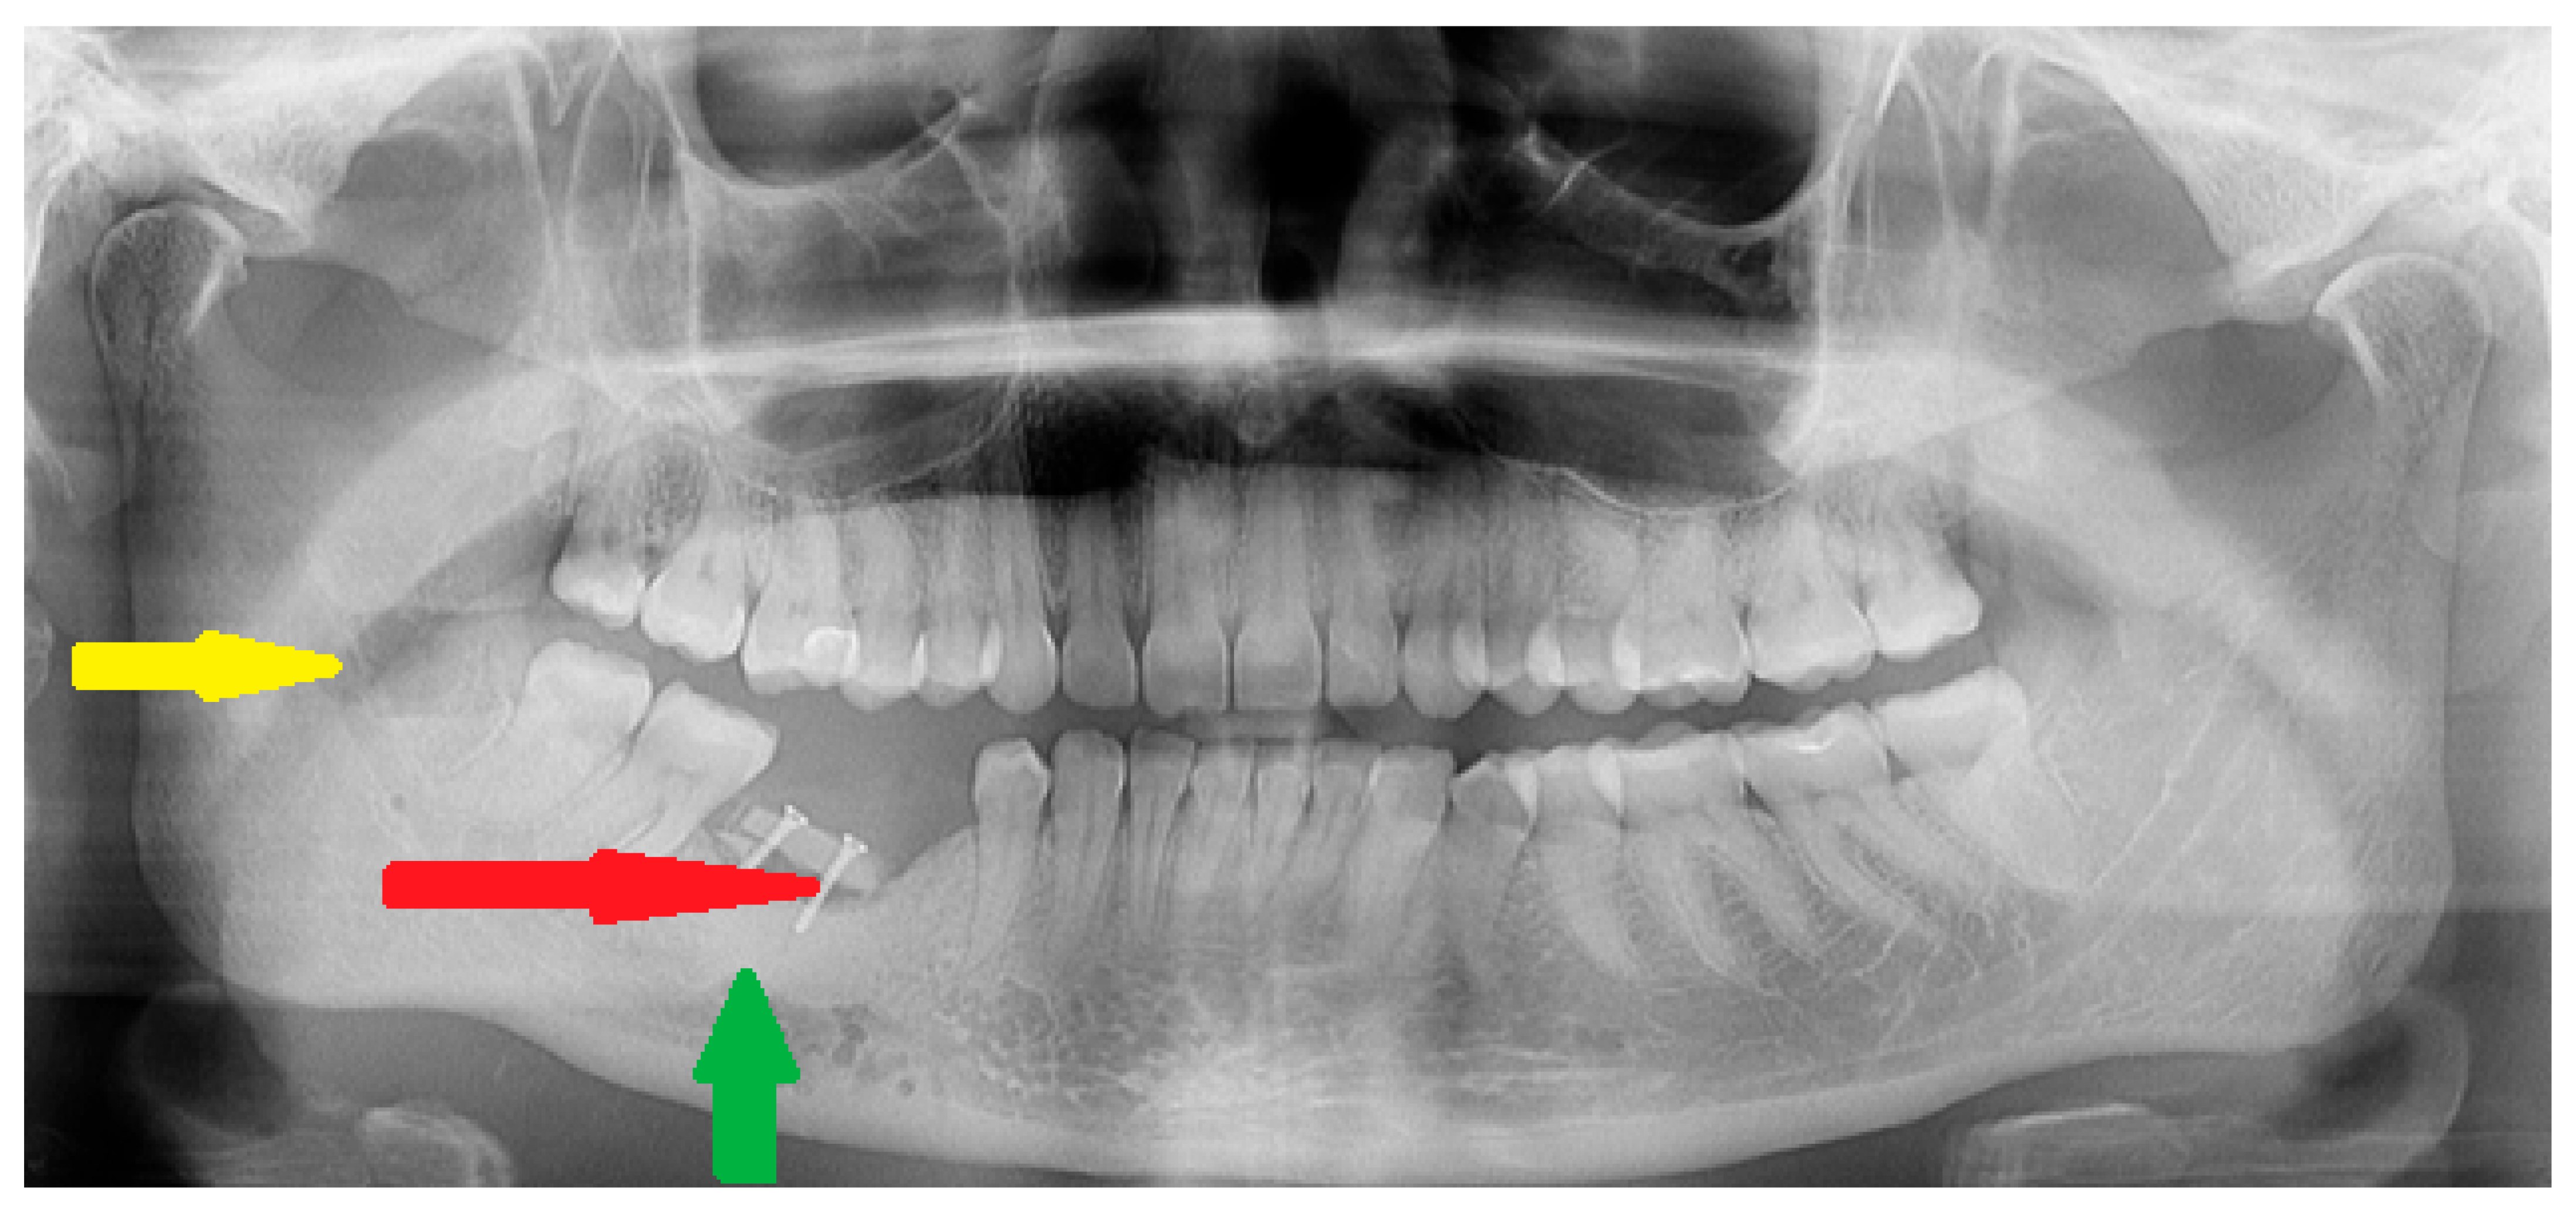

Figure 6. Final results at 24 months after surgery. Due to superior resorption of the previously placed allogenic bone, a decision was made to simultaneously remove the titanium plate, take a blind biopsy, and add some autologous bone graft transfer (red arrow) from the right mandible ramus (yellow arrow). This method was used to improve the height and diameter of the defect for future dental implant placement. Titanium bone grafting screws that were 1.2 mm/11 mm long were used to stabilize the grafted bone (Titamed, bone grafting screws PHI system, Kontich, Belgium). Significant bone remodeling after allogenic bone graft usage is evident (green arrow). Currently, the patient is free of the disease and awaits dental implant therapy.